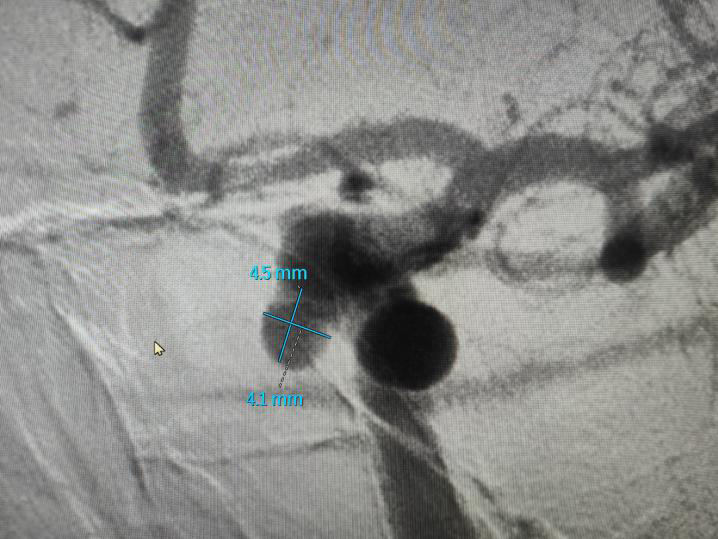

造影检查并做好手术预案:

密网支架(血流导向装置)治疗颅内动脉瘤效果: